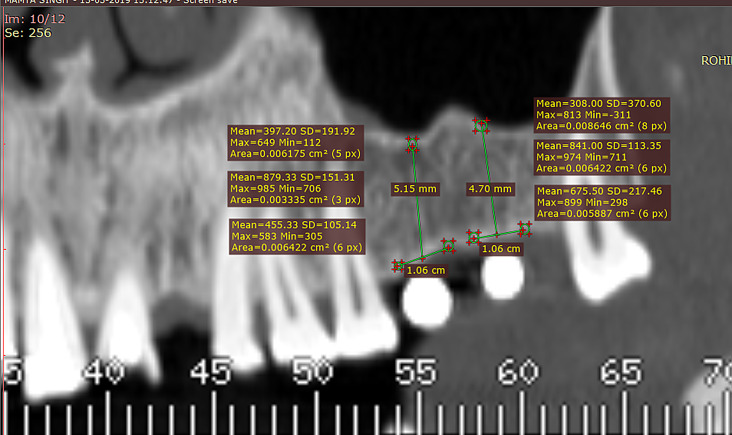

Methods: A total of 32 patients undergoing dental implant surgery were included in this study. Pre-operative and post-operative bone densities at the apical, mesial, and distal regions of the osteotomy sites were measured using Dentascan (CT) and analyzed with Radiant DICOM software. The study utilized osseodensification drills for osteotomy preparation, comparing pre-operative and post-operative bone densities to assess the technique's efficacy.

Results: The study found a statistically significant increase in bone density post-operatively (p < 0.001), with the greatest improvement observed in the distal region, followed by the mesial and apical regions. The findings underscore osseodensification's effectiveness in enhancing bone density and primary stability, with the distal region exhibiting the highest bone density.